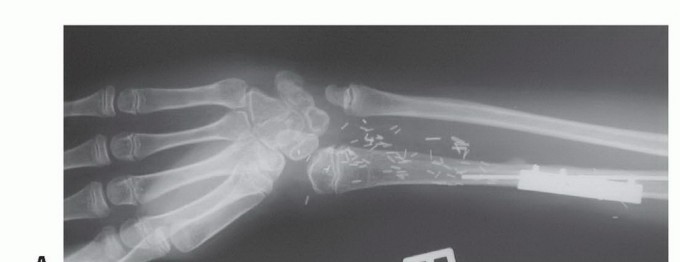

- الأشعة السينية العادية (Plain Radiography): تُظهر صور الأشعة السينية العادية (FIG 4AB) العيب العظمي وحجمه، وتساعد في تقييم بنية العظم المحيطة.

تصوير عيوب العظام

- أ. صورة شعاعية عادية للظنبوب تُظهر ساركوما عظمية كبيرة منخفضة الدرجة في الجزء الجذعي.

- ب. صورة شعاعية عادية للذراع تُظهر فقدانًا كبيرًا للعظم وكسرًا مرضيًا مرتبطًا بالتهاب العظم والنقي الحاد في جسم العضد.

- ج. إعادة بناء مقطعي محوسب إكليلي للساعد البعيد يُظهر ساركوما عظمية في الكعبرة البعيدة.